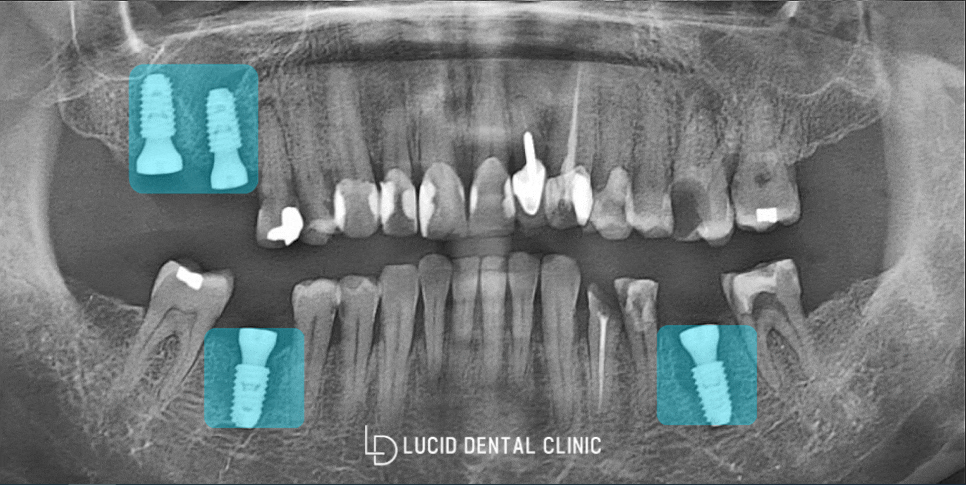

결과

뼈소실이 그렇게 크지 않았으며,

다른 질환 역시 제한될만한 것들이 없었기에

그리 어렵지 않게 픽스처 식립을 완료했습니다.

추후에 신논현역 치과 에 다시 들르셔서

현재 씌워놓은 임시치아를 제거 후,

크라운 세팅을 해드리기로 했습니다.

별일 없이 다시 뵙길 바라며

의료진은 환자분께 임시로 맞춰드린 것이니

쉽게 깨질 수 있어 조심스럽게

사용하는 것이 좋다는 당부 말씀을 드렸습니다.